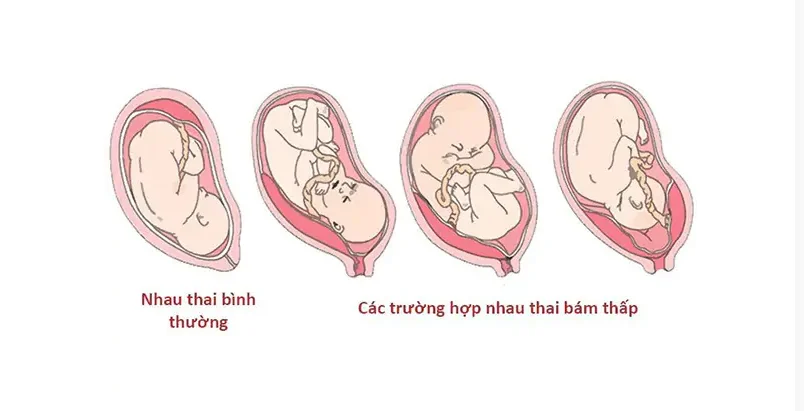

Nhau thai bám thấp là tình trạng khi bánh nhau không nằm ở vị trí bám đáy tử cung, mà thay vào đó một phần của bánh nhau bám ở đoạn dưới cổ tử cung, gần với cổ tử cung. Đây là một dạng nhẹ của nhau thai tiền đạo.

Vì bánh nhau nằm gần lỗ tử cung, tình trạng này dễ bị bong tách khỏi niêm mạc tử cung, gây ra hiện tượng xuất huyết cho người mẹ. Trong nhiều trường hợp tình trạng nhau bám thấp có thể được cải thiện khi thai lớn dần, và tử cung phát triển kéo bánh nhau lên cao.